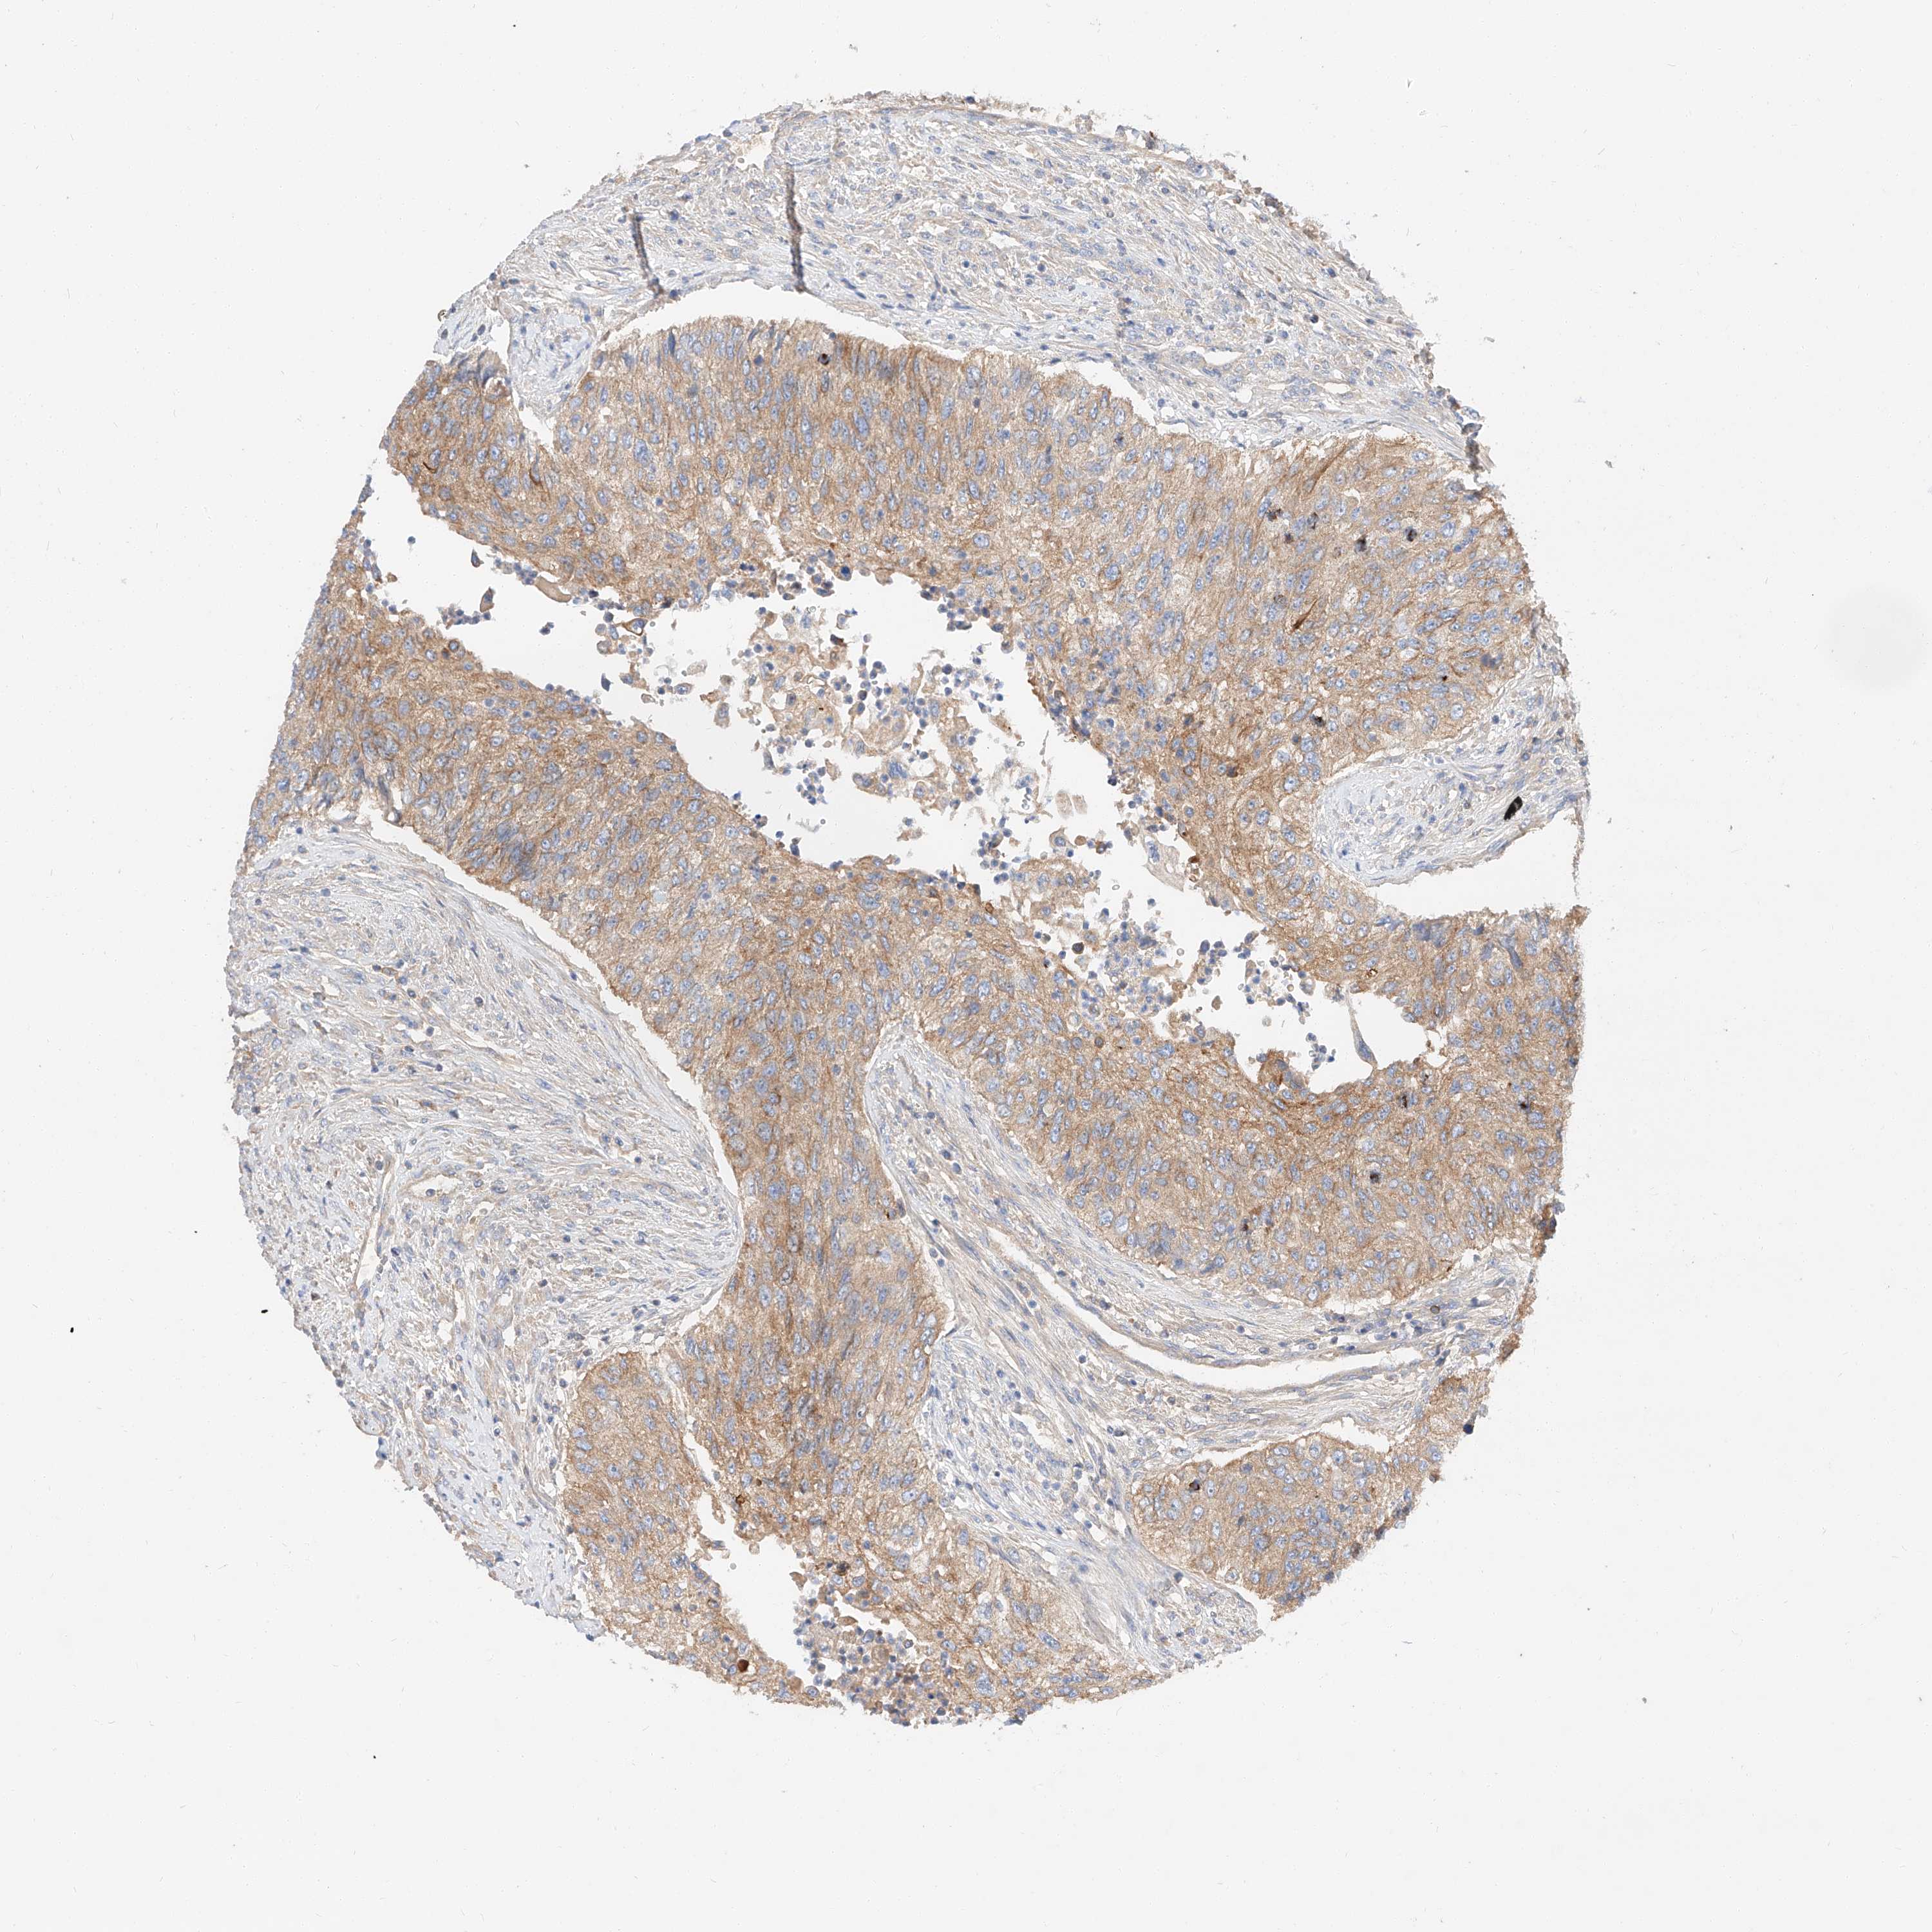

UROTHELIAL CANCER - Protein expressioni

A mouse-over function shows sample information and annotation data. Click on an image to view it in a full screen mode. Samples can be filtered based on level of antibody staining by selecting one or several of the following categories: high, medium, low and not detected. The assay and annotation is described here.

Note that samples used for immunohistochemistry by the Human Protein Atlas do not correspond to samples in the TCGA dataset.

Antibody stainingi

Antibody staining in the annotated cell types in the current human tissue is reported as not detected, low, medium, or high, based on conventional immunohistochemistry profiling in selected tissues. This score is based on the combination of the staining intensity and fraction of stained cells.

Each image is clickable and will lead to virtual microscopy that enables deeper exploration of all samples and also displays staining intensity scores, fraction scores and subcellular localization as well as patient and tissue information for each sample.

Antibody HPA029712

Antibody HPA029713

Staining

High

Medium

Low

Not detected

Intensity

Strong

Moderate

Weak

Negative

Quantity

>75%

75%-25%

<25%

None

Location

Nuclear

Cytoplasmic/membranous

Cytoplasmic/membranous,nuclear

Urothelial carcinoma, Low grade